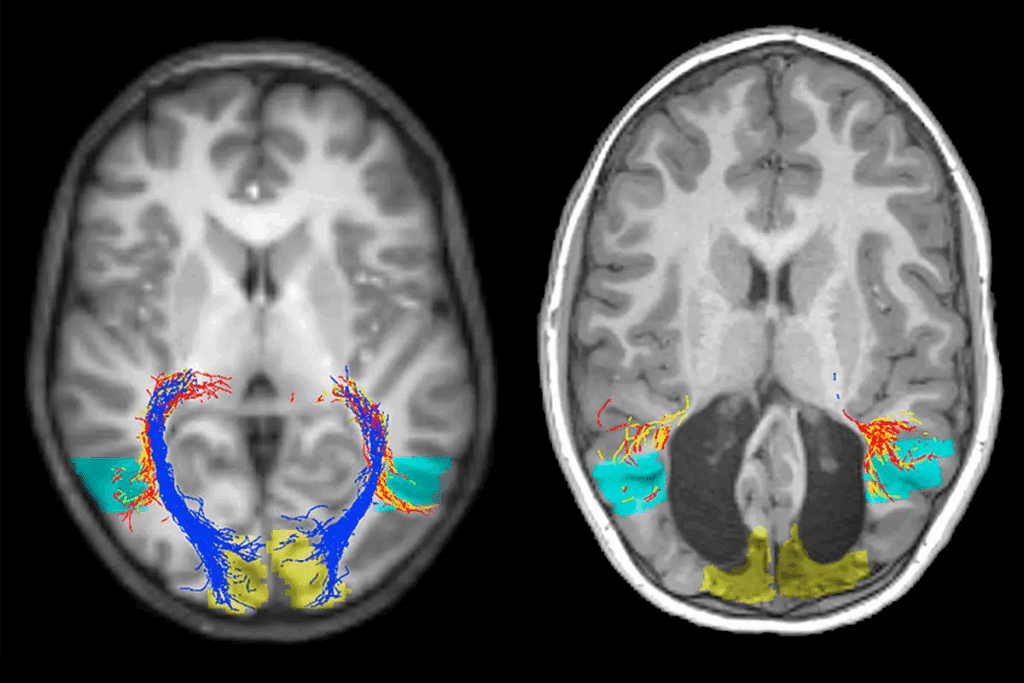

Advanced Imaging Techniques

Advanced imaging is vital for spotting brain metastasis. Magnetic Resonance Imaging (MRI) is our go-to tool. It gives us clear images and is very sensitive.

We also use Computed Tomography (CT) scans and Positron Emission Tomography (PET) scans. These help us learn more about the metastases and their effect on the brain.